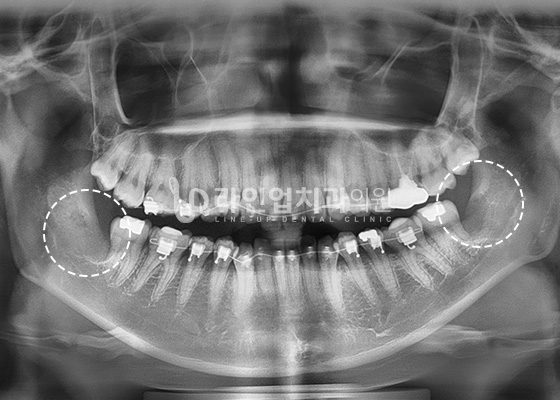

ПРИМЕРЫ УДАЛЕНИЯ ЗУБА МУДРОСТИ

Before

After